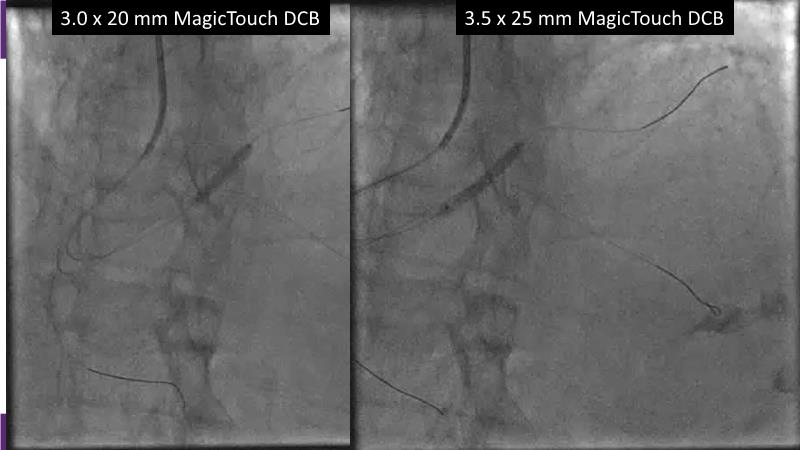

Consult this session to understand the technology and scientific evidence of the novel sirolimus drug-coated balloon, to learn its utility for PCI in a variety of lesion and patient subsets and to understand the evidence and outcomes in real-world patients.

- To learn the utility of the DCB for PCI in a variety of lesion and patient subsets